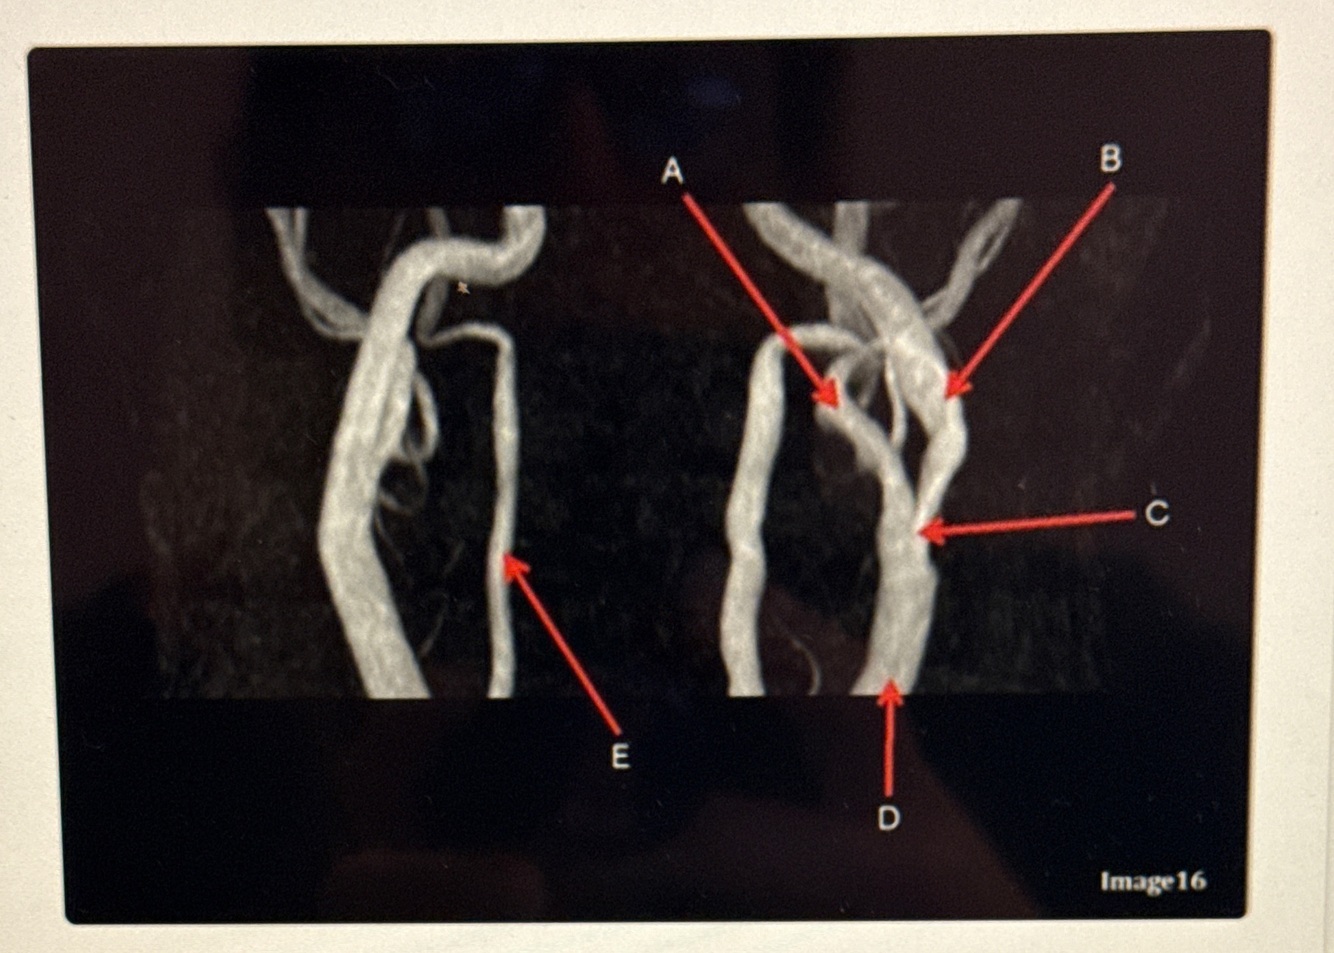

Letter A points to the

A

VertebroBasilar junction

Letter B points to the _______ and letter D points to the ______

B. External carotid artery

D. Vertebral artery